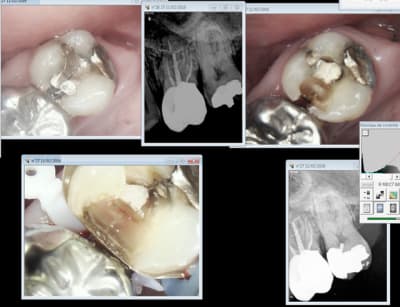

cher Marc faisons un peu de pédagogie.Voici un cas .Peut on le gérer seul avec une digue ET une aspiration en place non tenue sans que l 'hypochlorite ne coule dans le cou du patient Je crois que c'est possible

alors quelqu'un a t il une idée pour soigner ma petite patiente de 75 ans dans de bonnes conditions sans lui demander toutes les minutes de bien ouvrir et de pas tousser etc ....

je parle d 'un champ vraiment étanche ou tu risques pas de toucher la gencive et ou tu peux aller poster un message sur eugenol sans inquiétude même si la petite dame à plus toute sa tête (veridique)

ce cas a quelques années et la dent est toujours sur l 'arcade.La gencive à bourgeonné dans les caries de collet mais l 'espace biologique est ok